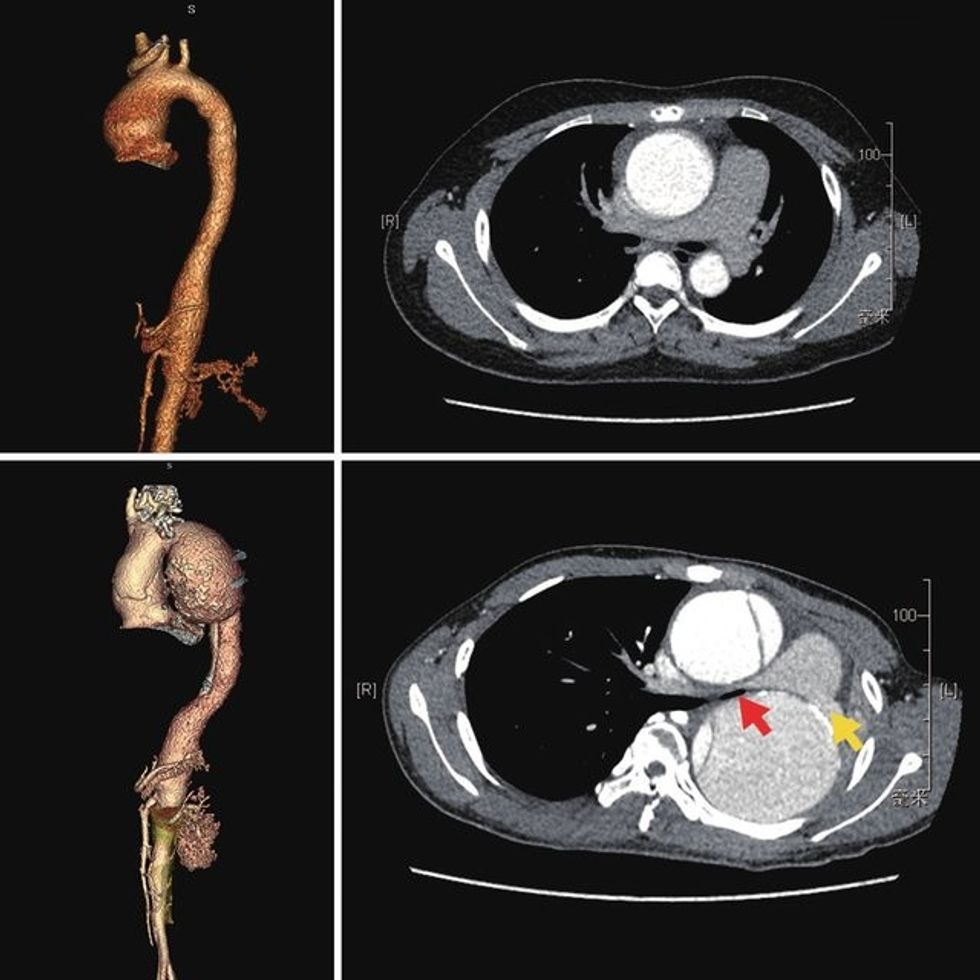

Aorta është enë gjaku elastike dhe me diametër (aorta ascendente 2.2-3.6cm; aorta descendente 2.0-3.0cm), por me kalimin e kohës muret e saj mund të dobësohen dhe rrjedhimisht të zgjerohet. Kjo quhet aneurizëm aorte. Në disa raste nën presionin e lartë e të pakontrolluar të gjakut, shtresat e aortës mund të çahen (shqyhen). Kjo quhet diseksion i aortës. Këto dhe disa sëmundje tjera të saj mund të komprometojnë funksionin jetik të aortës dhe në rastet kur ekziston kërcenim serioz i jetës së pacientit, vije në shprehje intervenimi kirurgjik i saj.

Metodat diagnostike kryesore për sëmundjet e aortës janë: Ekokardiografia, Angio MRI/CT, Aortografia, më rrallë PET Scan, IVUS.